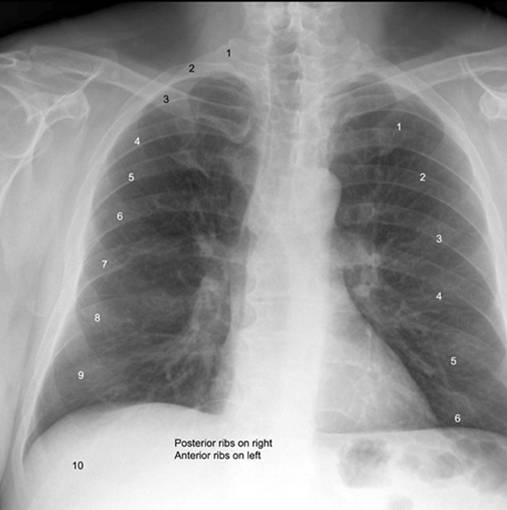

Basic Chest XRay Interpretation Tips and pointers to see it all!